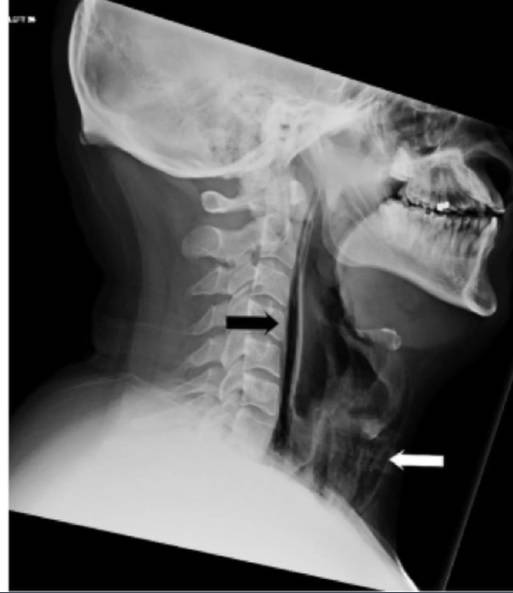

Quando i medici hanno esaminato il paziente hanno avvertito un crepitio su entrambi i lati del collo, un suono che si estendeva fino alla cassa toracica.

Questo sintomo si palesa quando ci sono bolle d’aria nel tessuto sotto la pelle.

Quindi hanno effettuato delle scan hanno notato una bolla di capelli intrappolata sotto la pelle dell’uomo, la maggior parte nella regione del collo.

La scan ha mostrato anche bolle d’aria nel petto, nella parte tra i polmoni, una condizione chiamata pneumodiastimo.

Secondo i medici lo starnuto represso ha causato un buco nella parte profonda della laringe, o della gola, dove c’è la connessione con l’esofago.